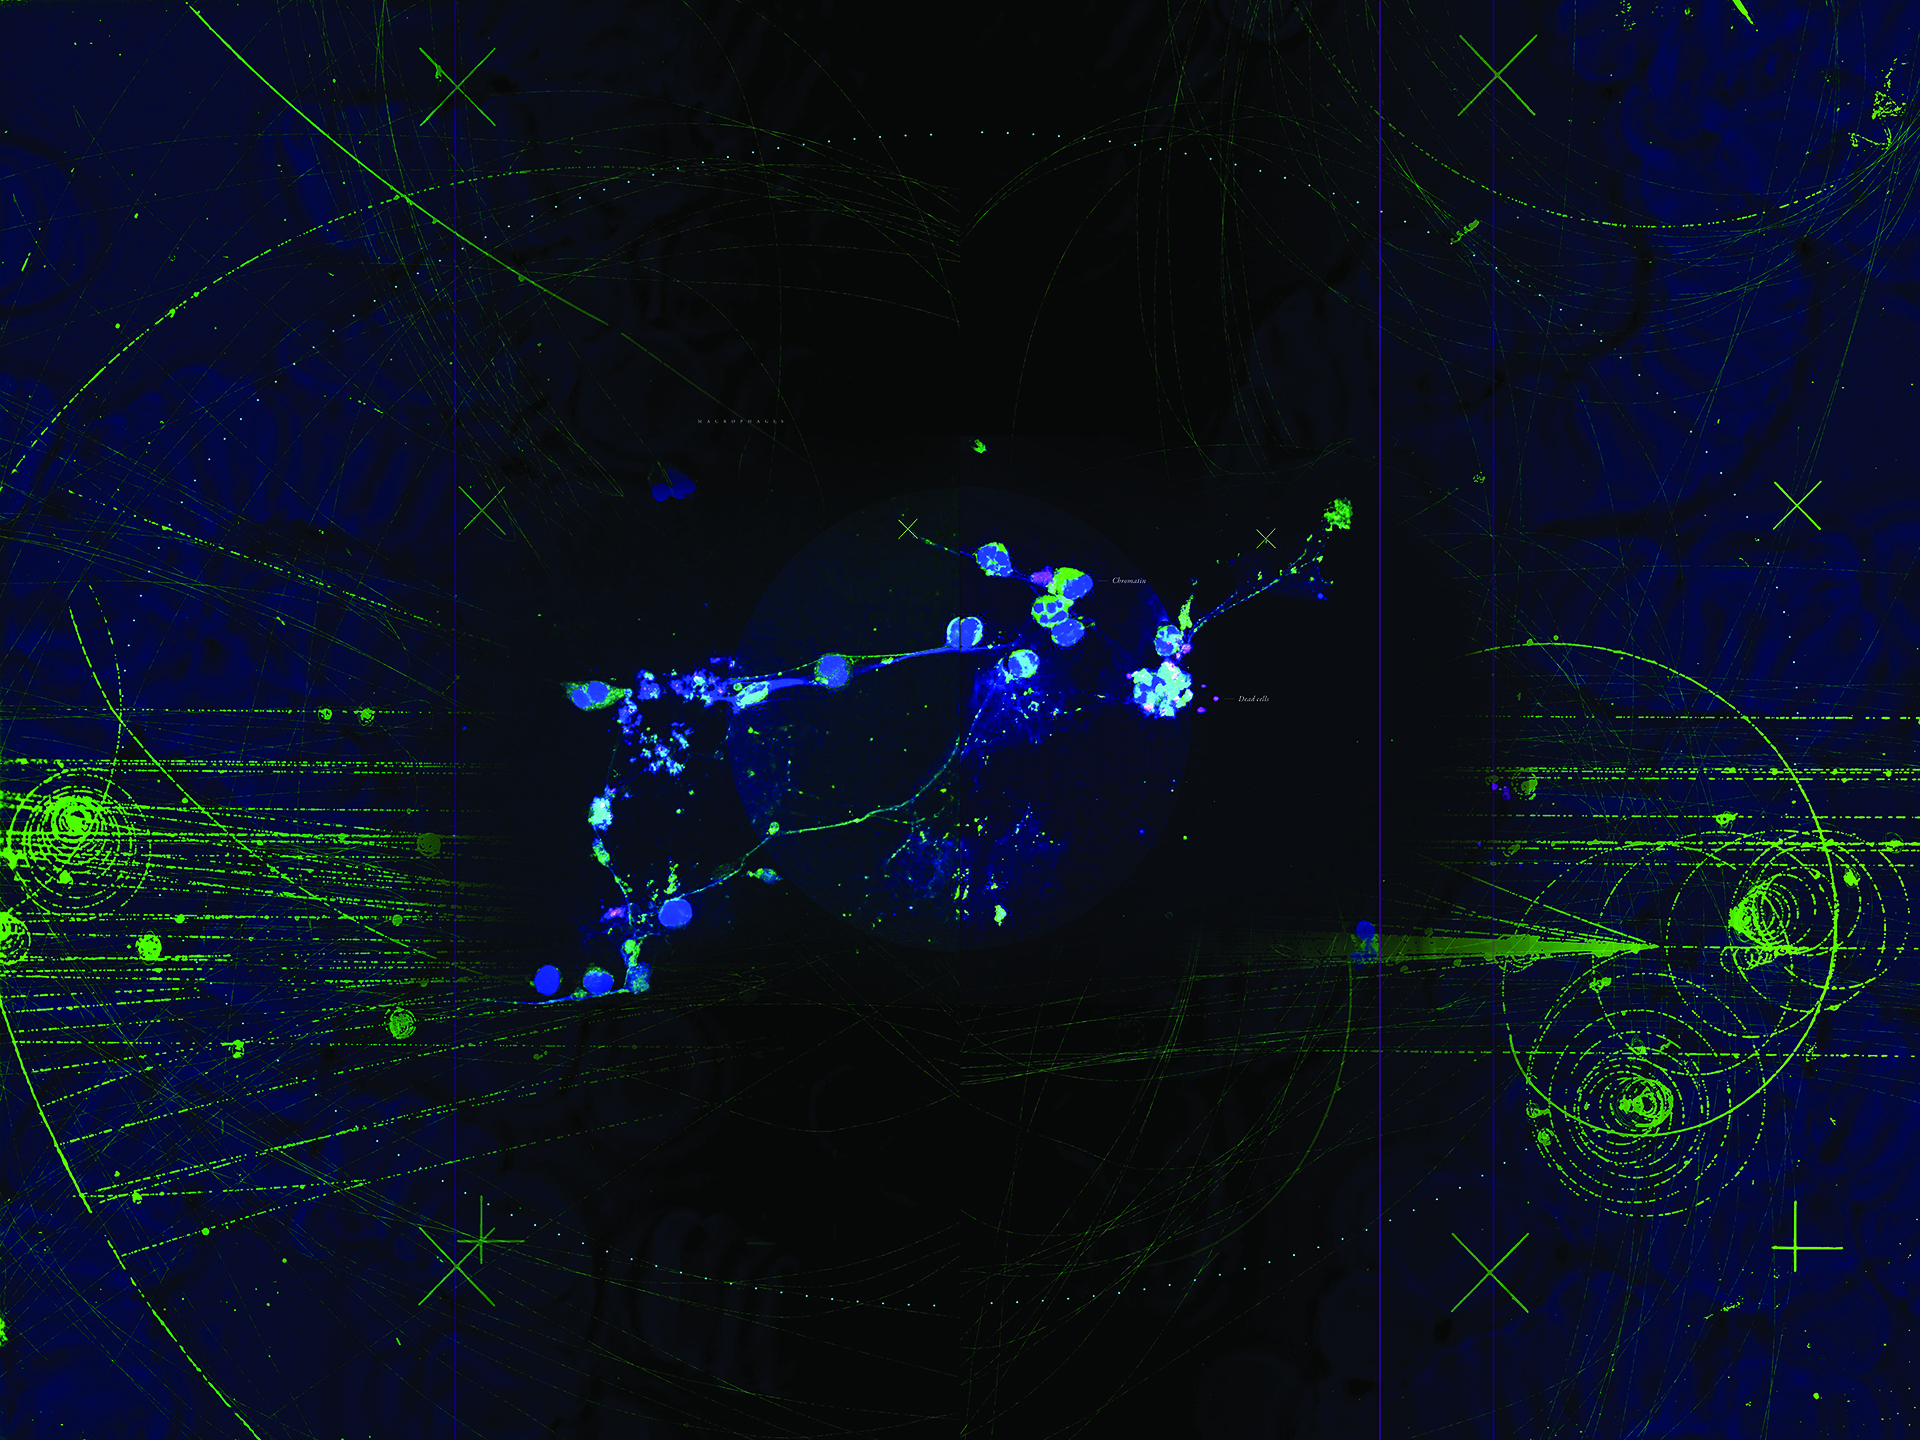

Pathogens are a major factor affecting the evolution of primates. We know very little about how historical pandemics have affected the genomes of different populations. This image results from research that examines how genetic variation and historical exposure to one of the most virulent pathogens known in human history, the plague, has affected immune system evolution and human health.

In the center of this image we see human white blood cells (labeled blue) confronted with bacteria. To protect the body from this invader, the cells capture the bacteria by throwing nets made from their own DNA. The cells are laid over tracks that evoke those seen in bubble chambers, another innovation used by researchers to see into the smallest spaces and understand movement and action on the smallest scales.